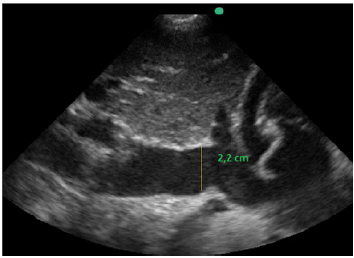

Também foi feita a mensuração da cava na janela subcostal 4 câmaras caval. O seu valor é maior de 2,2 cm e tem variabiliadade menor que 50% aos movimentos respiratórios ainda em ventilação espontânea, conforme a imagem apresentada.

Com base nessas informações e nas imagens, a estimativa da pressão sistólica da artéria pulmonar é de